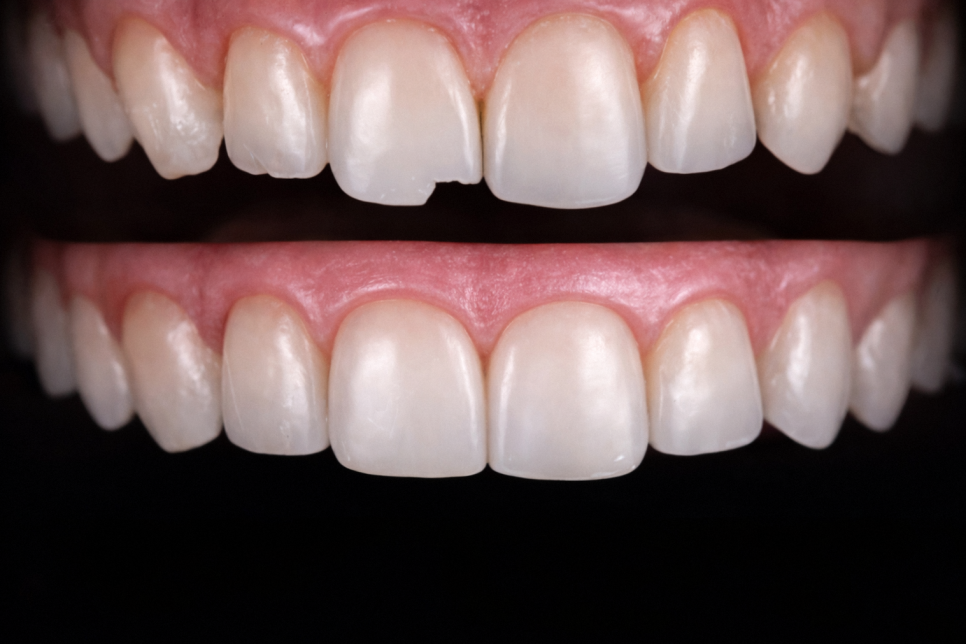

- 라미네이트가 필요한 경우

손상 범위가 더 넓거나

심미성의 중요도가 높은 분에게는

라미네이트를 권유 드립니다.

앞니는 작은 차이만 있어도 부각되기 때문에,

라미네이트의 얇고 정밀한 마감이

심미적인 완성도를 높이는 데 유리합니다.

강도와 변색 가능성도 적기 때문에

장기적으로 외형을 유지할 수 있습니다.